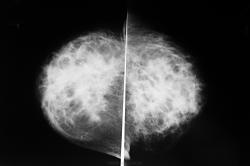

Видимо компьютер не очень хорошо передает изображение, на снимках не видно утолщенной кожи и подкожной клетчатки, только тени участков отека железы, сглаженность структурных элементов. все это видно при  сравнении со здоровой железой. Справа - вторая железа этой же  женщины?  Предлагаю для демонстации утолщение кожи за счет отека.

Приложения:

otek_kozhi_1-2.jpg